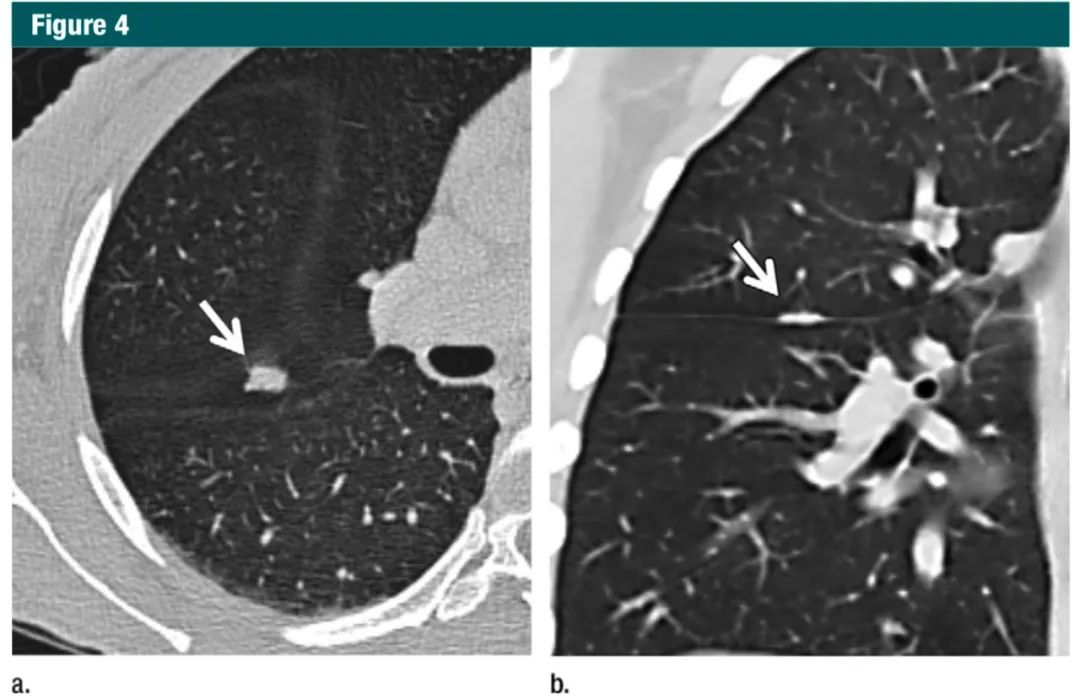

使用厚层观测病灶会增大平均体积,使小结节的特征显示不准确,对于部分实性形态和脂肪或钙化成分的结节,则会影响管理方案(图 1-3)。冠状位和矢状位序列能有助于区分结节和瘢痕(图 4)。这个建议并不局限于专门为结节评估或筛查肺癌而进行的检查,因为任何成人都有可能偶发肺结节。如果初次检查用的是厚层,为了对比,那么短期内还需要做薄层 CT 随访。

图4:a.横断面1mm层厚CT显示靠近水平裂的一个结节样致密影(箭头);b.CT冠状位重建显示该致密影是良性的线状疤痕或淋巴组织(箭头)7Gc帝国网站管理系统